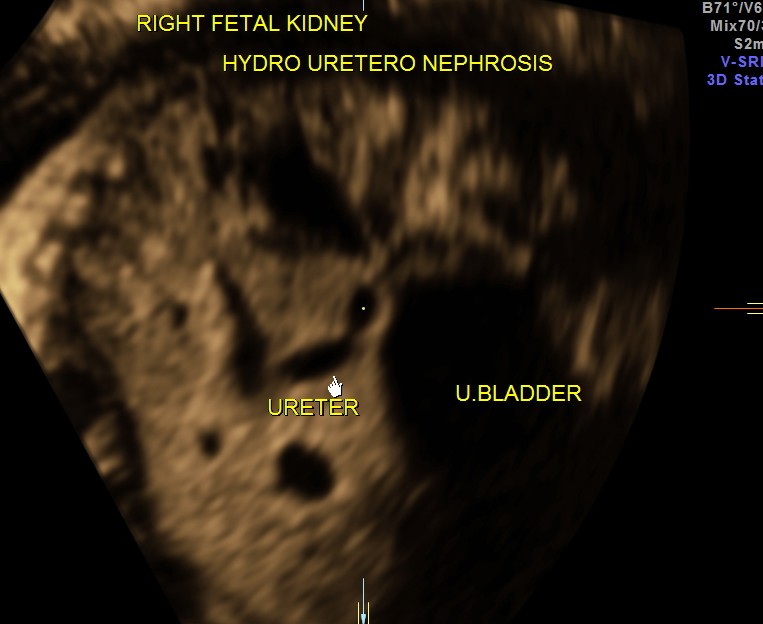

The fetus also showed bilateral pelvi calyectasis and rt ureteromegaly.